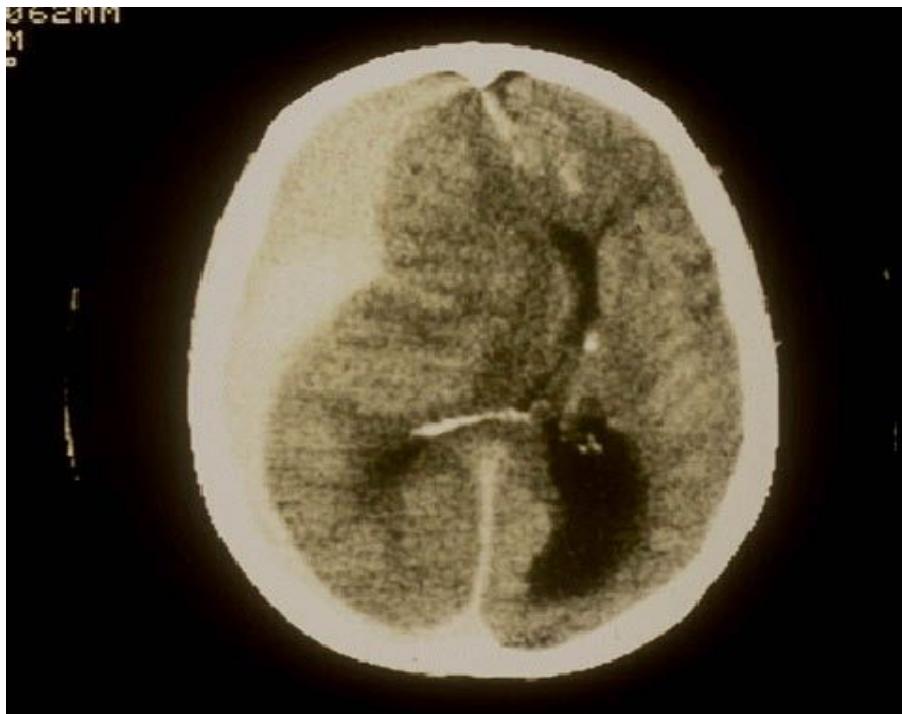

Intracerebral Hemorrhage

- Diagnosis: Intracerebral Hemorrhage.

- CT Finding: Hyperdensity within the brain parenchyma.